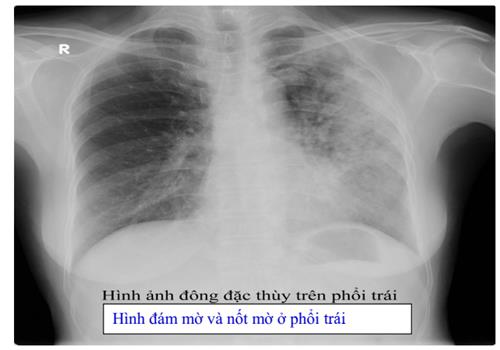

- Xquang phổi thường quy: hình ảnh trên phim X-quang gợi ý lao phổi tiến triển là thâm nhiễm, nốt, hang, có thể 1 bên hoặc 2 bên. Ở người có HIV, hình ảnh X-quang phổi ít thấy hình hang, hay gặp tổn thương tổ chức kẽ và có thể ở vùng thấp của phổi. X-quang phổi có giá trị sàng lọc cao với độ nhạy trên 90% với các trường hợp lao phổi AFB(+). Cần tăng cường sử dụng X-quang phổi tại các cơ sở y tế cho các trường hợp có triệu chứng hô hấp để sàng lọc lao phổi. Tuy nhiên cần lưu ý độ đặc hiệu không cao, nên không khẳng định chẩn đoán lao phổi chỉ bằng 1 phim X-quang phổi. Xquang phổi còn có tác dụng đánh giá đáp ứng với điều trị thử bằng kháng sinh thông thường trước khi chẩn đoán lao phổi không có bằng chứng vi khuẩn và để đánh giá kế quả điều trị lao sau 2 tháng và kết thúc điều trị.

+ Lao phổi: ở giai đoạn lâm sàng nhiễm HIV sớm, khi sức đề kháng chưa ảnh hưởng nhiều, hình ảnh tổn thương trên X-quang ngực không khác biệt so với ở người HIV âm tính. Ở giai đoạn muộn, tổn thương thường lan tỏa 2 phế trường với những hình ảnh tổn thương dạng nốt, ưu thế tổ chức liên kết lan tỏa, ít thấy hình ảnh hang, có thể gặp hình ảnh hạch rốn phổi, hạch cạnh phế quản … cần phân biệt với viêm phổi do Pneumocystis Carinii (PCP).